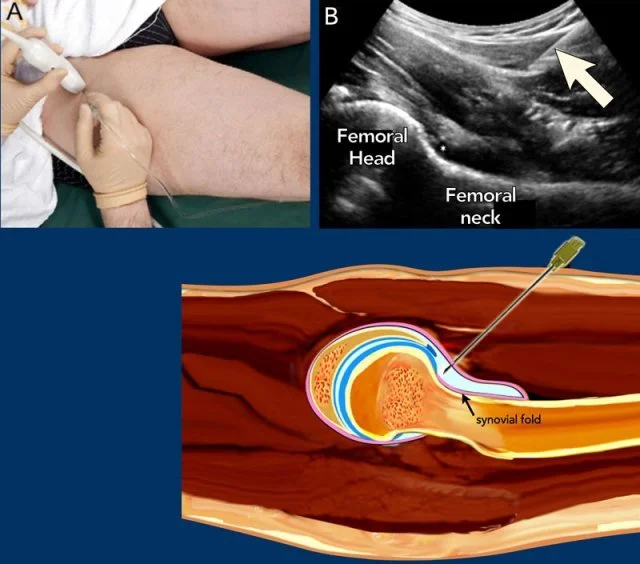

• Cells are harvested via a simple outpatient procedure like aspiration, minimally processed on-site, and returned to targeted areas like joints under imaging guidance.